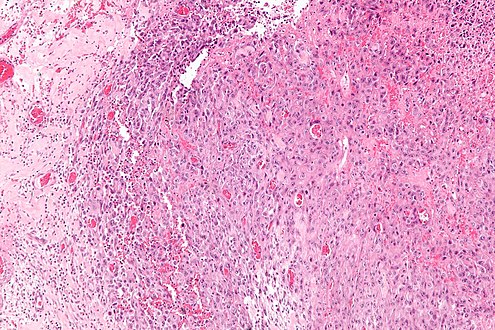

| Micrograph of an epithelioid sarcoma. H&E stain. | |

Histologically, epithelioid sarcoma forms nodules with central necrosis surrounded by bland, polygonal cells with eosinophilic cytoplasm and peripheral spindling.[3] Epithelioid sarcomas typically express vimentin, cytokeratins, epithelial membrane antigen, and CD34, whereas they are usually negative for S100, desmin, and FLI1 (FLI-1).[3] They typically stain positive for CA125.[4]

Tissue biopsy is the diagnostic modality of choice. Due to a high incidence of lymph node involvement, a sentinel lymph node biopsy is often performed. A common characteristic of epithelioid sarcoma (observed in 80% of all cases) is the loss of function of the SMARCB1 gene (also termed BAF47, INI1, or hSNF5). Immunohistochemical staining of INI1 is available and can be used for the diagnosis of epithelioid sarcoma. MRI is the diagnostic modality of choice for imaging prior to biopsy and pathologic diagnosis, with the primary role being the determination of anatomic boundaries.[citation needed]

Intermed. mag.